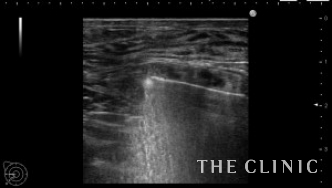

術前のエコーです。

乳腺下に充実性のしこりがあります。右はカプセル内ですがしこりは移動しませんでした。左はカプセル内を広範囲に移動します。他にも1.5㎝の小さなしこりもありこれも移動します。